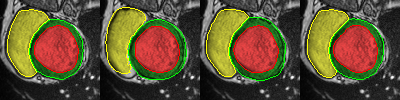

Careful inspection reveal that errors are not uniformly distributed. Interestingly, conv-deconv and U-Net produce accurate results on most slices of each 3D volume as illustrated in the first two rows of Fig. 2. That said, they often get to generate a distorted result for 1 or 2 slices (out of 7 to 17) which end up decreasing the Dice score and increasing the Hausdorff distance. This situation is shown in rows 3,4, and 5 of Fig. 2. Overall, the right ventricle is the most challenging region for all three methods. It is especially true at the base of the heart, next to the mitral valve where the RV is connected to the pulmonary artery. This is illustrated in the last row of Fig. 2.